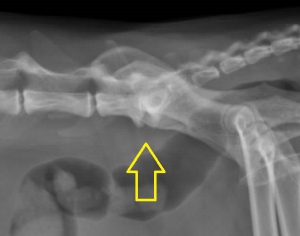

下のレントゲン写真がそういった変形性脊椎症で、椎骨が不安定化している部分には棘のように見える骨棘(こつきょく)がみられます。このような例では腰の部分を触ろうとすると強い痛みを訴えて、排便や排尿に支障がみられることもしばしばです。